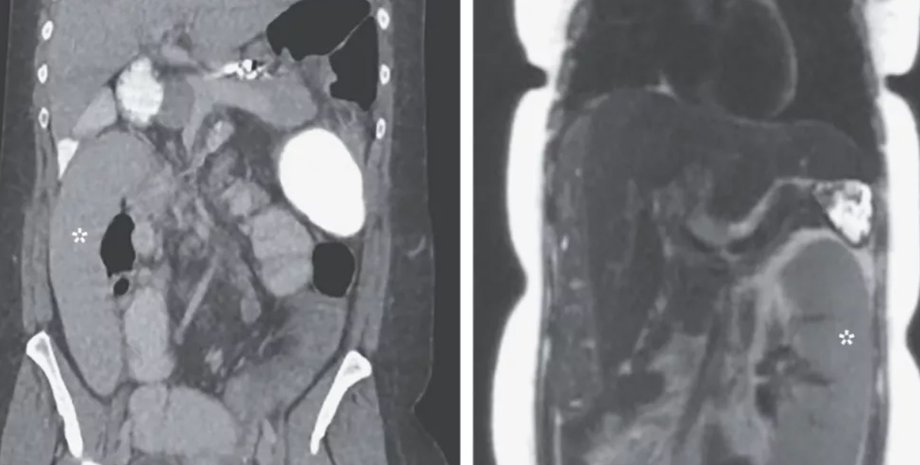

Фото: The New England Journal of Medicine

Когда 36-летняя женщина поступила в больницу Michigan Medicine в городе Энн-Арбор, врачи обнаружили ее селезенку в правом нижнем квадранте живота.

До того, как пациентка попала в больницу с "блуждающей селезенкой", она прошла обследование на рак печени, во время которого были сделаны медицинские снимки живот и селезенка была на своем месте. Через день у женщины появились боли в животе и рвота.

В отделении неотложной помощи врачи сделали новое сканирование, выяснив, что селезенка переместилась на противоположную сторону тела пациентки.